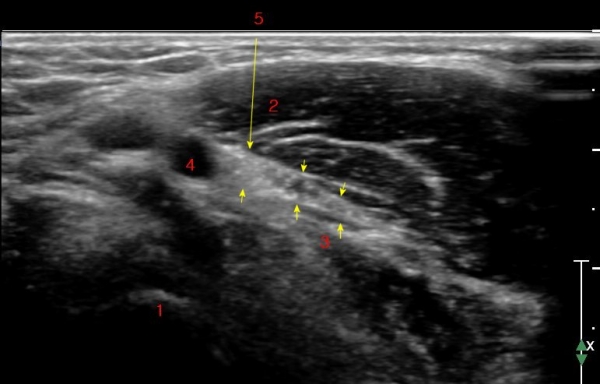

ÃÊÀ½ÆÄ °Ë»ç : ȸ³»±Ù ±ÙÀ§ºÎ¿¡¼ Á¤Á߽Űæ Ⱦ´Ü¸é°Å»ç¿¡¼ ƯÀÌ ¼Ò°ßÀ» º¸ÀÌÁö ¾ÊÀ¸³ª(»çÁø 1) ȸ³»±Ù ¿ä°ñµÎ ±â½ÃºÎ ¿¡¼ Á¤Á߽ŰæÀÇ ±¹°íÀû ¾Ð¹Ú ¹× ÆíÆòȰ¡ °üÂûµÊ(»çÁø 2). ÀÌ·± º¯È´Â °ÇÃø(»çÁø 5)°ú ºñ±³ÇÏ¸é ¶Ñ·ÇÇÔ.

Á¤Á߽Űæ Á¾´Ü¸é°Ë»ç¿¡¼ ȸ³»±Ù ¿ä°ñµÎ ±â½ÃºÎ¿¡¼ Á¤Á߽ŰæÀÇ ±¹¼ÒÀû ¾Ð¹Ú°ú Ç¥ÃþÀ¸·Î ÀüÀ§°¡ °üÂûµÇ°í ¾Ð¹ÚÀÇ ±ÙÀ§ºÎ¿¡¼´Â Á¤Áß½Å°æ ºÎÁ¾ÀÌ °üÂûµÊ(»çÁö 3). ÀÌ·± º¯È´Â °ÇÃø(»çÁø 6)°ú ºñ±³ÇÏ¸ç ¶Ñ·ÇÇÔ.